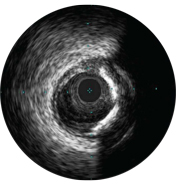

На мальаппозицию указывает наличие крови за стратами стента. При визуализации с использованием режима ChromaFlo кровоток окрашен в красный цвет для простого выявления мальаппозиции и других особенностей просвета.

Степень раскрытия стента является предиктором тромбоза стента и рестеноза. Целевая минимальная площадь стента после ЧКВ может включать ≥ 80% референсных площадей просвета, 6 мм2 для стентов с лекарственным покрытием в сосудах, не относящихся к ЛКА, или другие критерии в зависимости от типа ЧКВ. ВСУЗИ помогает задокументировать полученные результаты2.